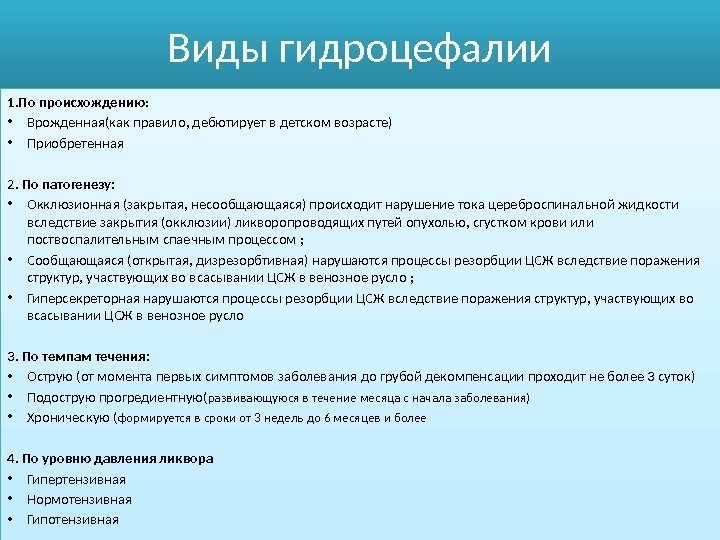

Признаки умеренно выраженной наружная

Признаки умеренно выраженной наружная 113 фото